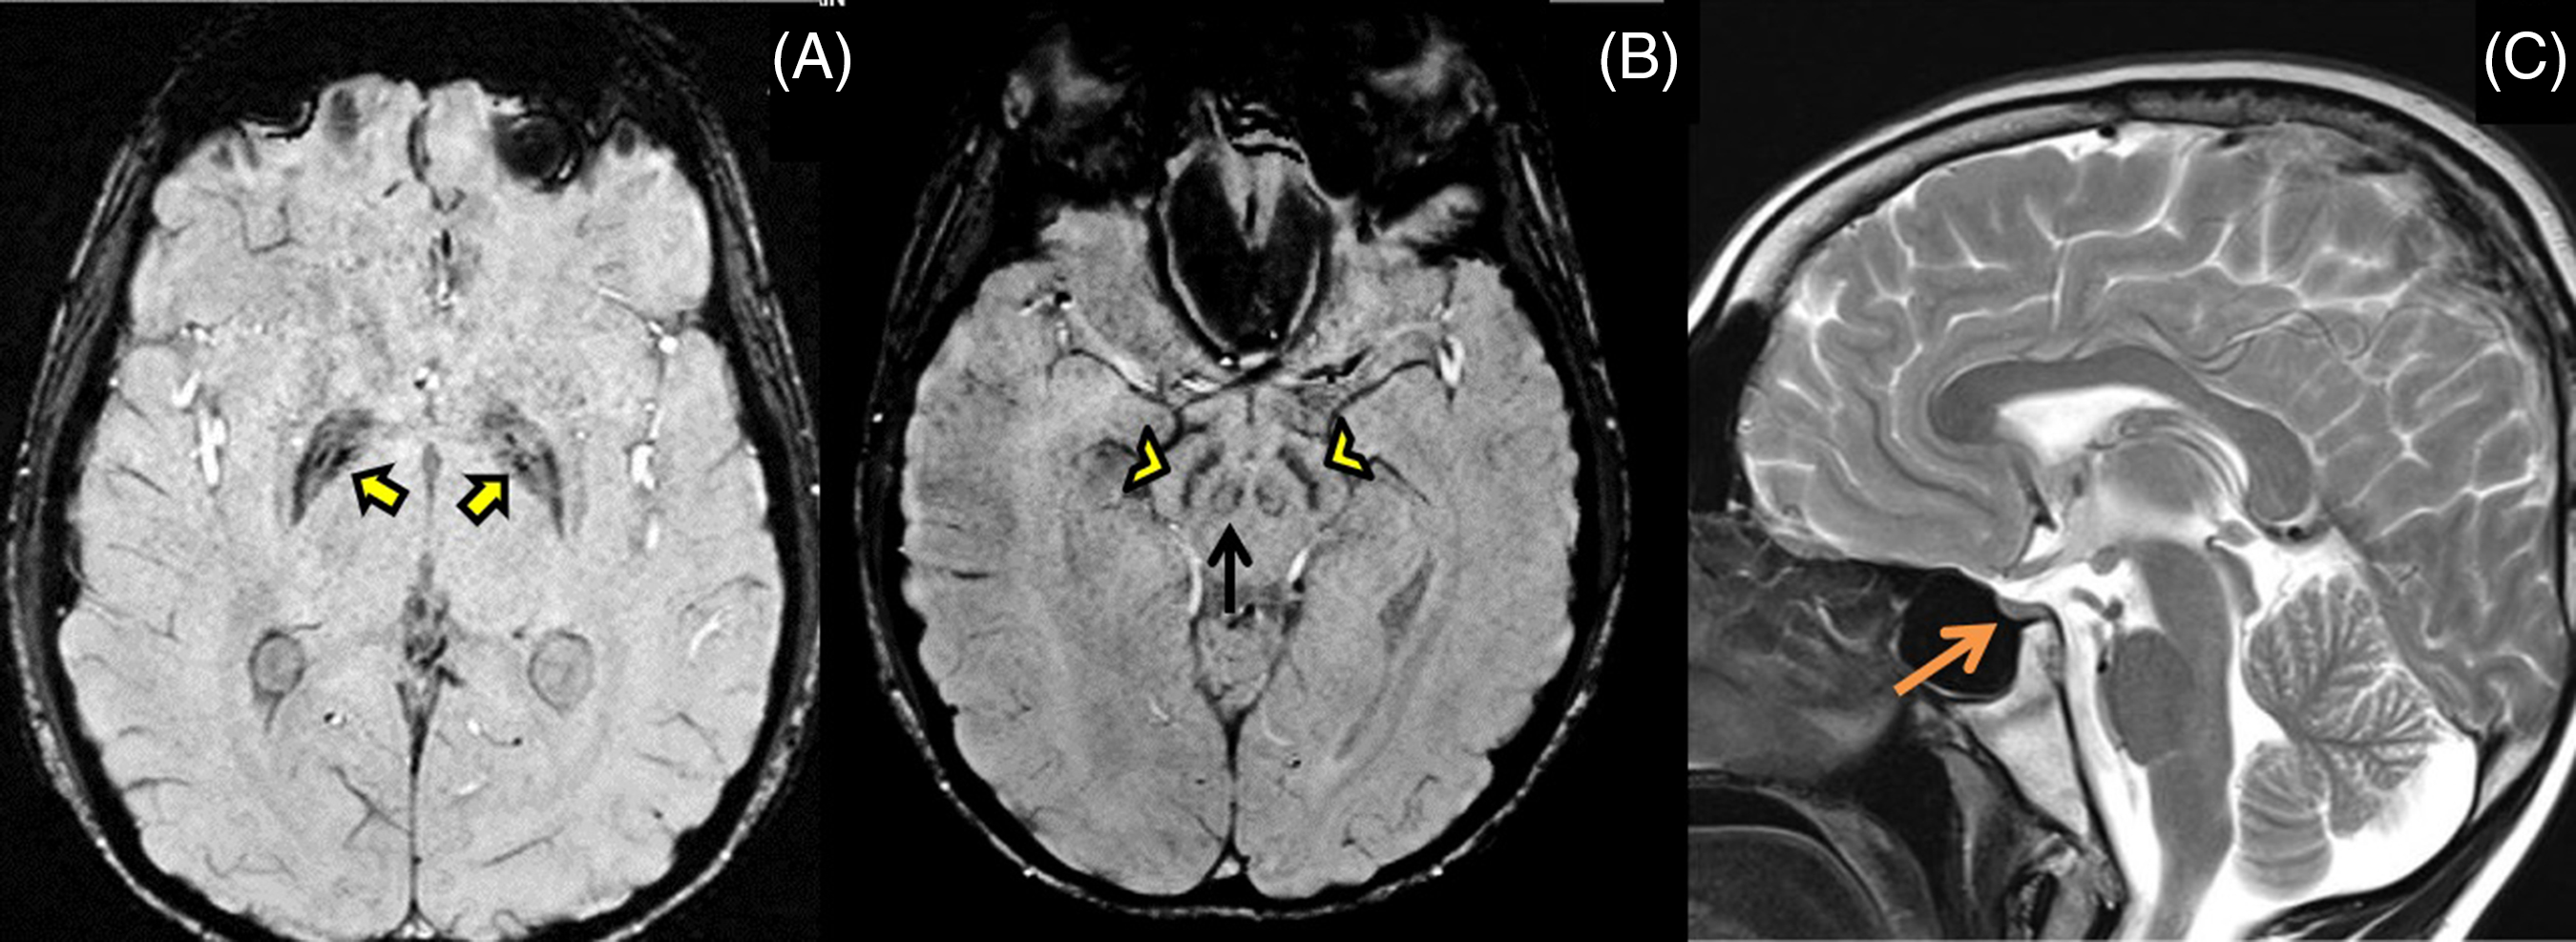

The proband’s 19-year-old brother also had writer’s cramp since 8 years of age which later became non-task specific. He did not have lower limb symptoms, tremors, parkinsonism, or ataxia. He was poor scholastically, had similar sparse scalp hair and impaired secondary sexual characters. Examination revealed action dystonia of both upper extremities (right > left) on writing and other tasks (Video segment 3 and 4). His MRI brain showed iron deposition in bilateral globus pallidus and substantia nigra on SWI images (Figure 2A, B) and a small-sized pituitary gland on T2 weighted images (Figure 2C) with no white matter changes. He had diabetes and a hormonal profile suggesting hypogonadotropic hypogonadism.

Figure 2: MRI brain shows mineralization in bilateral globus pallidus (yellow arrows), substantia nigra (yellow arrowheads) and red nucleus (black arrow) on SWI images (A,B), and small-sized pituitary gland (orange arrow) on T2 weighted images (C) with no white matter changes.